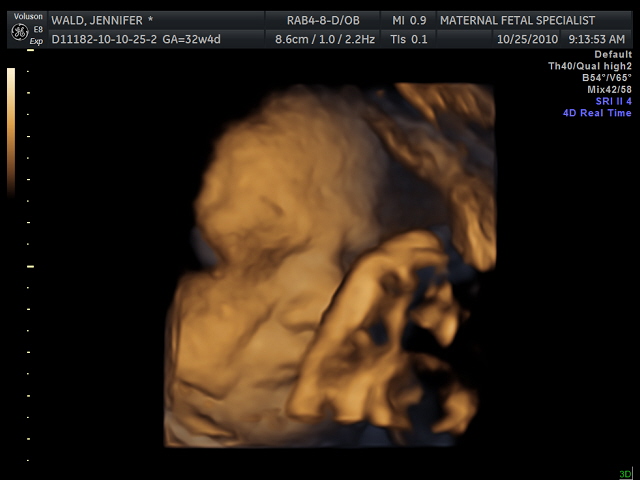

This was a total surprise. Being as I have had this same blood sugar issue for the last few weeks, I was shocked by this chain of events. However, we did as we were told and went in. Once we got there, they proceeded exactly as planned. A very quick ultra sound followed by the amnio. We were then told that because I am 38 weeks, and as long as her lungs were fully developed, there was not reason to wait another week to induce and they would just induce me tonight. They said that while my low blood sugars were not concrete evidence that something was wrong, it was definitely suggestive. Being as she is fully developed, it makes more sense to have her out then to wait to see if something goes wrong.